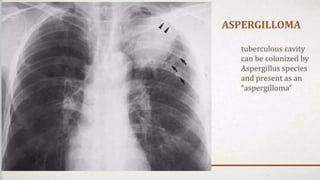

THORACO-ABDOMINAL SIGN